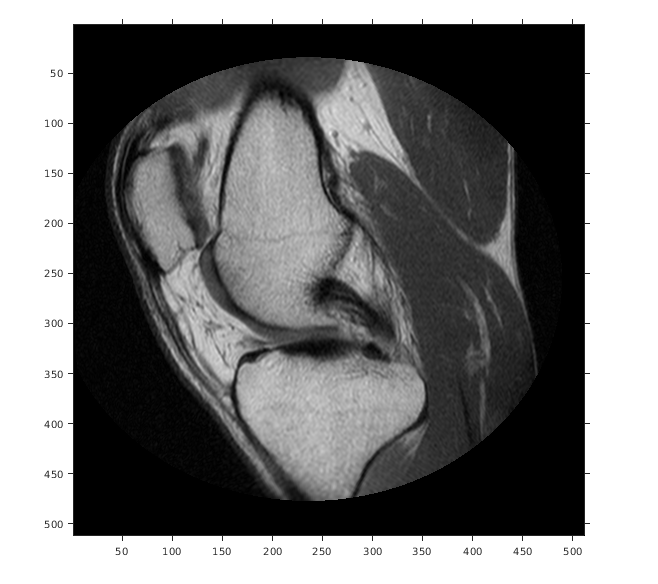

Отобразите изображение, не использовав пространственный ссылочный объект. Координаты осей отражают внутренние координаты. Заметьте, что координата (0,0) находится в левом верхнем углу.

figure

imshow(A,'DisplayRange',[0 512])

axis on

Предположим, что вы хотите вычислить аппроксимированное положение и ширину колена в миллиметрах. Выберите конечные точки линейного сегмента, который запускается горизонтально через колено на уровне коленной чашечки. Например, используйте (x, y) точки (34,172) и (442,172).

xIntrinsic = [34 442];

yIntrinsic = [172 172];

Преобразуйте эти точки от внутренних координат до мировых координат.

[xWorld,yWorld] = intrinsicToWorld(RA,xIntrinsic,yIntrinsic)

xWorld = 1×2

10.6250  138.1250

yWorld = 1×2

53.7500   53.7500

Мировые координаты двух точек (10.625,53.75) и (138.125,53.75) в модулях миллиметров. Аппроксимированная ширина колена в миллиметрах:

width = xWorld(2) - xWorld(1)

width = 127.5000